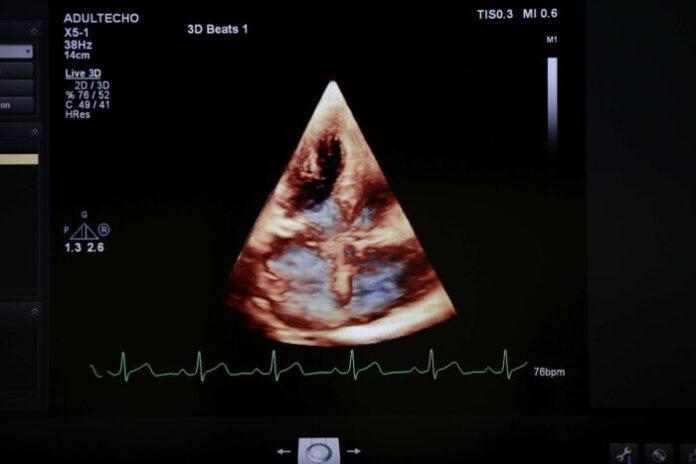

“การซักประวัติ ตรวจร่างกาย และการใช้หูฟังฟังเสียงหัวใจของแพทย์เป็นวิธีการนำมาซึ่งการวินิจฉัยโรคหัวใจที่ดี แต่บ่อยครั้งอาจไม่เพียงพอ ต้องอาศัยการตรวจเพิ่มเติมที่ละเอียดมากขึ้น ปัจจุบันมีการตรวจเพิ่มเติมทางด้านหัวใจหลายประเภท และมีจุดเด่นและข้อจำกัดแตกต่างกัน ดังนั้น ผู้ป่วยบางรายอาจต้องได้รับการตรวจเพิ่มเติมมากกว่าหนึ่งชนิด เช่น การตรวจคลื่นไฟฟ้าหัวใจหรือ EKG; การตรวจวิ่งสายพานหรือ Stress Test; การตรวจทางภาพถ่ายรังสีแบบธรรมดา จนถึง เอ็กซ์เรย์คอมพิวเตอร์ หรือ เอ็กซเรย์คลื่นแม่เหล็กไฟฟ้า หรือ CT scan cardiac MRI; การฉีดสีหลอดเลือดหัวใจ และการตรวจที่จัดได้ว่าเป็นหนึ่งในการตรวจที่สำคัญที่สุด คือ การตรวจด้วยคลื่นเสียงสะท้อนหัวใจขั้นสูง (Echocardiography)” รศ.พญ.ศริญญา อธิบายเพิ่มเติม